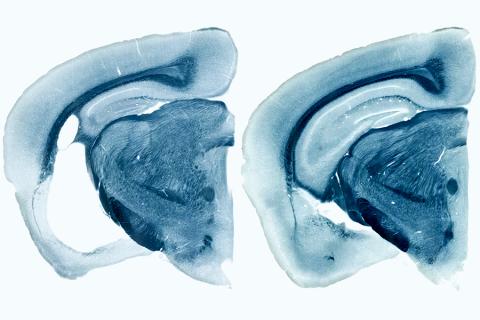

"타우"에 대한 검색 결과 총 8 건 생명과학·의학 연합뉴스 2025-08-28 알츠하이머의 두 원인단백질 서로 소통하며 독성 조절한다 타우 미세소관 결합 부위와 아밀로이드 베타와의 상호작용 ⓒKAIST 제공 알츠하이머의 두 원인 단백질이 서로 소통하며 독성을 조절한다는 연구 결과가 나왔다. 한국과학기술원(KAIST) 임미희 교수와 한국기초과학지원연구원 이영호 박사, 한국과학기술연구원(KIST) 김윤경·임성수 박사 공동 연구팀은 알츠하이머병의 주요 병리 기초·응용과학 권예슬 리포터 2025-06-13 치매 예방하는 ‘마사지’, 효과 입증했다 약물이나 수술이 아닌 마사지가 치매 예방에 도움이 된다는 연구 결과가 나왔다. 기초과학연구원(IBS) 혈관 연구단은 뇌 대사활동의 부산물로 생긴 노폐물이 배출되는 경로를 밝힌 데 이어, 이 경로에 물리적 자극을 가하면 노화로 저하된 뇌척수액 배출 기능이 회복됨을 동물 실험을 통해 확인했다. 연구결과는 지난 5일 최고 권위의 국제학술지 ‘네이처(Nature)’에 실렸다. 생명과학·의학 연합뉴스 2024-12-23 알츠하이머 치료제 나올까…타우 단백질 제거 원리 밝혀 한미 공동 연구팀이 알츠하이머병의 원인이 되는 타우 단백질이 제거되는 원리를 밝혔다. 한국생명공학연구원 이정수 박사 연구팀은 한국과학기술연구원(KIST) 류훈 박사 연구팀, 미국 보스턴 의과대학 이정희 교수 연구팀과 함께 '발로신 함유 단백질'(VCP)의 타우 단백질 제거 기능을 확인했다고 18일 밝혔다. 알츠하이머병은 치매를 일으키는 생명과학·의학 김병희 객원기자 2020-07-30 “피검사로 알츠하이머병 조기 발견한다” 미국 워싱턴대 의대 신경학과 랜달 베이트먼 교수팀은 알츠하이머병의 한 원인으로 지목되는 타우 단백질 조각인 p-tau-217이 발병 수년 전부터 농도가 올라간다는 사실을 발견하고 혈액 속 미량의 단백질 성분을 감지해 발병을 예측할 수 있는 방법을 개발했다. 생명과학·의학 김병희 객원기자 2020-02-10 알츠하이머 발병 타우 단백질 구조 밝혀 알츠하이머병의 주범으로 최근 새롭게 주목받는 타우(Tau) 단백질의 세부 구조와 독성 기전의 윤곽이 미국 연구진에 의해 밝혀졌다. 타우 단백질은 오랫동안 알츠하이머병과 다른 많은 신경성 뇌질환에 연루돼 있었으나, 과학자들은 그동안 이 단백질이 정상적으로 기능을 발휘하다 어떻게 잘못 접힌 유해한 단백질로 변환되는지 정확하게 이해하지 못했었다. 기초·응용과학 이강봉 객원기자 2019-07-17 여성 알츠하이머 환자가 더 많은 이유? 17일 ‘LA 타임스’는 14일부터 18일까지 LA에서 열리고 있는 ‘국제 알츠하이머 학술대회’에서 다수의 과학자들이 새로 발견한 유전자를 증거로 제시하면서 여성의 뇌에서 남성보다 더 빨리 알츠하이머 증상이 확산되고 있는 원인을 설명하고 있다고 보도했다. 과학자들이 가장 많이 지목하고 있는 유전자는 ‘APOE-e4’ 돌연변이 유전자다. 이 유전자는 LDL 콜레스테롤 수치를 높이는 역할을 하고 있다. 이 콜레스테롤 수치가 높아지면 동맥이 막혀 심장마비와 뇌졸중의 위험이 높아질 수 있다. 생명과학·의학 김병희 객원기자 2018-12-17 "알츠하이머 단백질 전파될 수 있다" 알츠하이머병도 전염될 수 있을까? 지금까지 알츠하이머병은 활동성 병원체에 의한 것이라기보다 비정상적인 단백질이 뇌혈관에 침착돼 발병하는 것으로 알려져 있어 전염 가능성 얘기는 거의 없었다. 기초·응용과학 김병희 객원기자 2017-09-21 알츠하이머병 치료 길 열릴까? ApoE4의 존재가 다른 알츠하이머 관련 단백질인 타우(tau)의 독성 엉킴으로 인한 뇌 손상을 악화시킨다는 사실이 밝혀졌다. 처음 페이지로 이동 이전 페이지로 이동 1 다음 페이지로 이동 마지막 페이지로 이동 처음 페이지로 이동 이전 페이지로 이동 1 다음 페이지로 이동 마지막 페이지로 이동